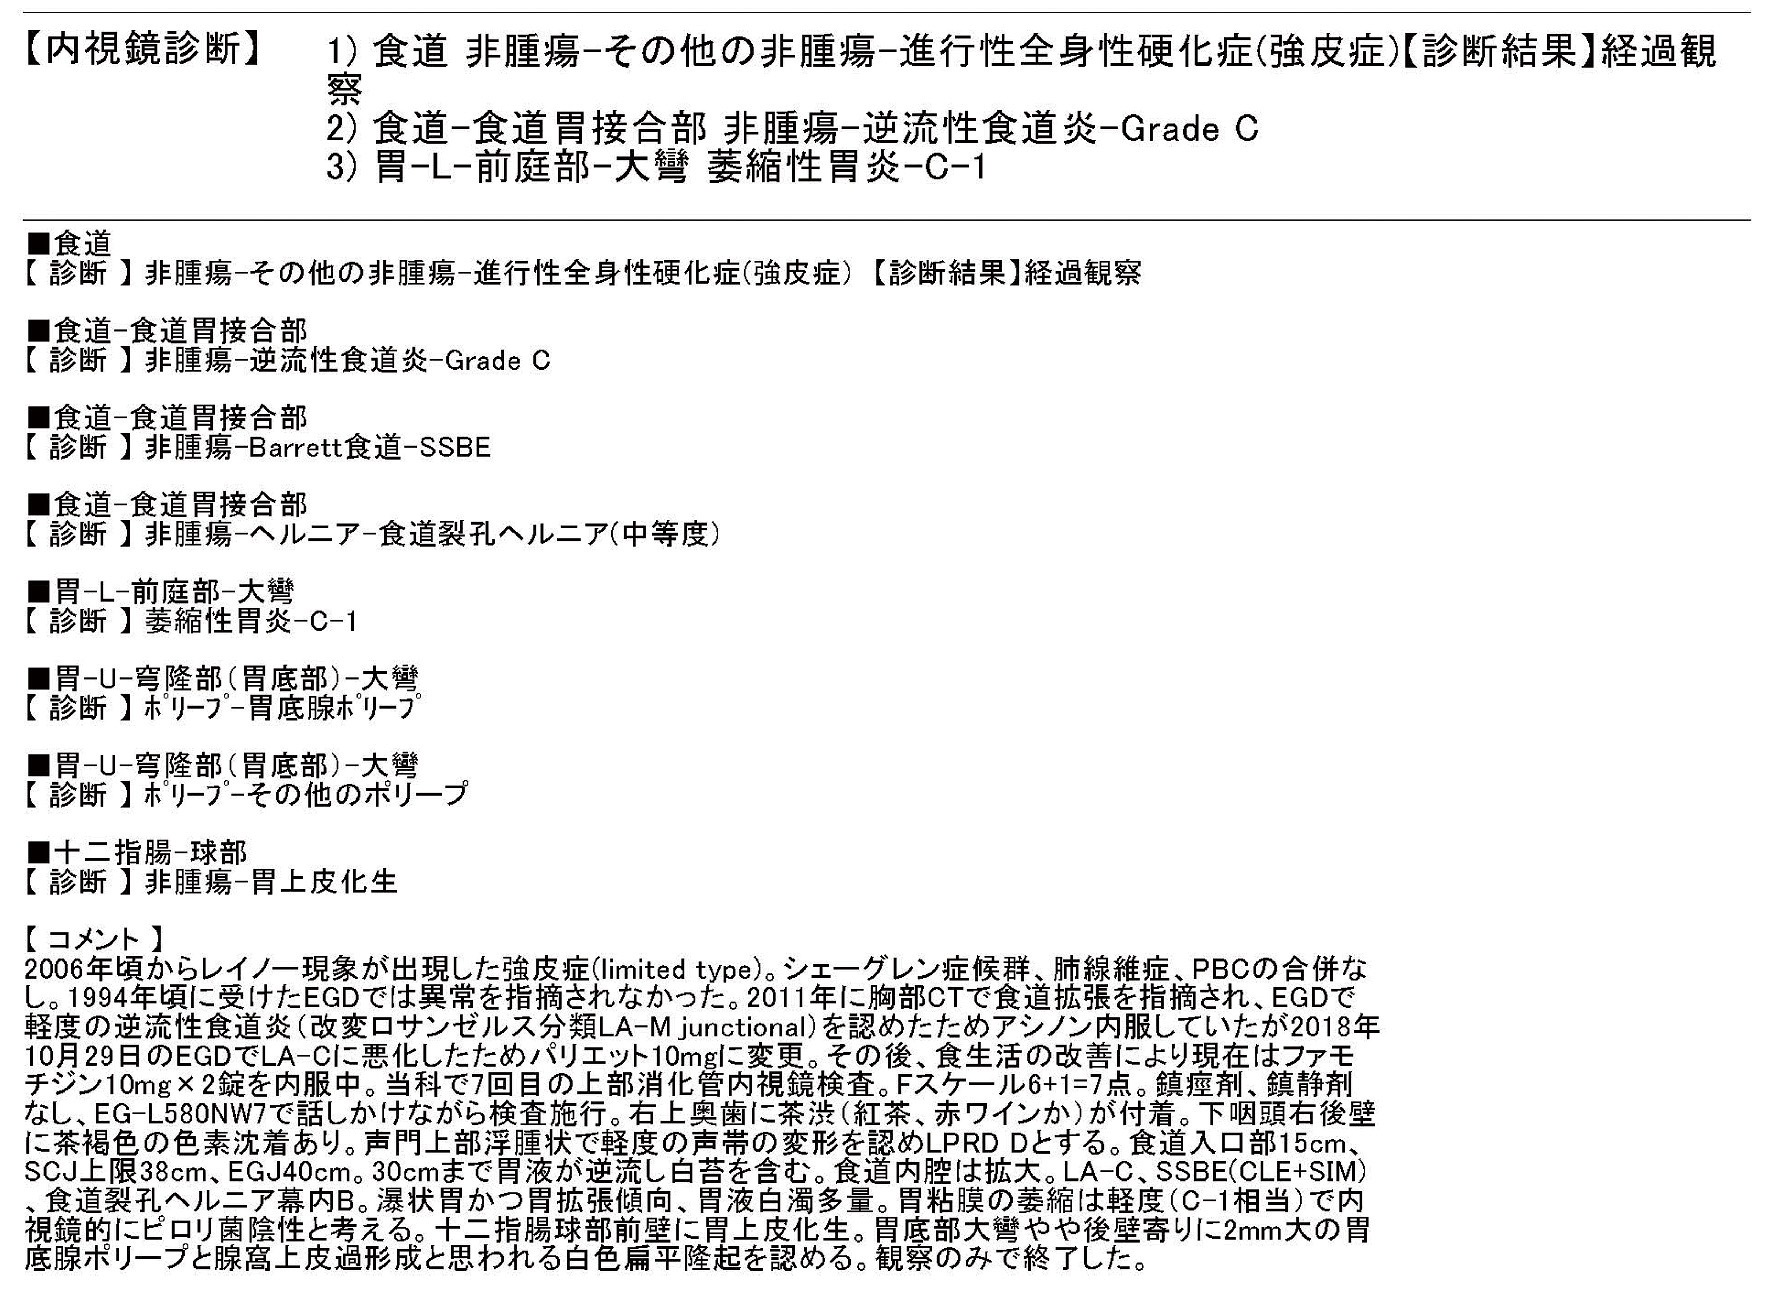

【症例2】60歳代,女性.

主訴:胃もたれ,圧迫時の胃痛

既往歴など:H. pyloriの除菌歴なし.非喫煙,非飲酒.

悪性腫瘍の家族歴:兄,食道癌.姉,大腸癌.

内服歴:ランソプラゾール15mg/日

内視鏡検査法:鎮痙剤なし,鎮静剤:ミダゾラム0.9 mL,炭酸ガス送気使用,経口挿入.IEE (NBI) 併用.

使用機種:GIF–H290 (オリンパス,面順次方式電子内視鏡)

検査場所:増山胃腸科クリニック (大田原市,増山仁徳院長)

内視鏡画像:ⓔ動画11-1-5 (144枚の静止画を連続再生)

内視鏡検査所見・診断:report (図2) 参照

検査時間:12分

撮影枚数:144枚

生検結果:Group 1 fundic gland polyp